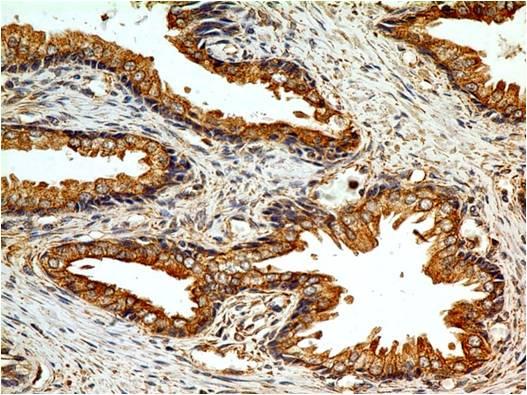

| Application: | FACS, IF, WB, IHC |

Western blot analysis: 2-4 µg/ml, FACS analysis: 0.5 µg/10^6 cells, Immunohistochemical analysis: 5 µg/ml